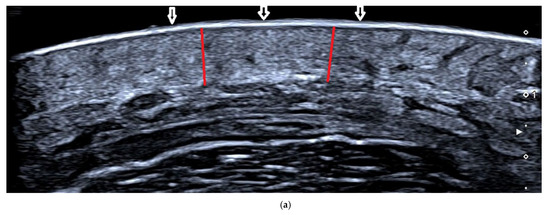

Figure 3.

Ultrasonic images of patients four weeks before and after treatment. (a) AFL+MTX group patient 4 weeks before treatment. The uppermost layer, the epidermis layer, is hyperechoic (shown with white arrows), and the underlying dermis is hypoechoic (shown with red line) and indistinguishable from the fat layer. (b) AFL+MTX group patient 4 weeks after treatment. The dermis is thinner than before (shown with red line) and can be easily distinguished from the fat layer. (c) AFL group patient 4 weeks before treatment. The dermis (shown with blue line) is indistinguishable from the fat layer. (d) AFL group patient 4 weeks after treatment. The dermis is thinner (shown with blue line) than before and clearly identified with the fat layer.